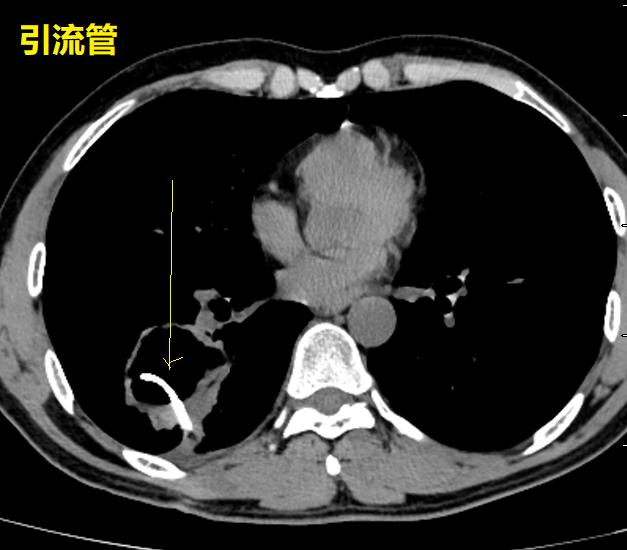

外院不知道为什么就考虑肺脓肿,还在“脓腔”里面放一大个引流管。这种骚操作,不容易见到。各位请看。

首先,我们不得不承认,这个放引流管的水平,确实高!就像洲际导弹,准确的命中目标,引流管放在了空洞的正中央。

这个空洞,是个典型的肺鳞癌。根本就没有必要放个引流管。

首先,患者没有明显的感染症状!其次,这个空洞没有气液平,也不像肺脓肿。最后,这个空洞乱糟糟的,有些地方壁厚,有些地方壁薄,空洞里面凹凸不平,空洞周围边界清晰,没有炎症反应引起的模糊阴影。外加患者是中年人,基本上就是肺鳞癌。

肺鳞癌放个大管子,没有用,极少数情况下,还可能导致肿瘤播散。